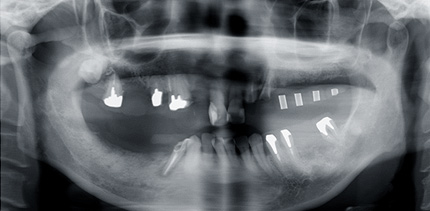

![]() |

X線撮影用ステントをいれたレントゲンです。むかって左上白い部分にインプラントがはいる予定です。 |

当院では、インプラントのオペの前にステントを装着しCTによる顎の骨の分析を行います。 |

この状態でインプラントを埋入すると隣の自分の歯と接蝕してしまうこと、また骨が不足しているので骨造成が必要なことがわかりました。修正が必要です。

撮影用ステントにより得られた情報を基に修正してサージカルステントにします。サージカルステントとはX線撮影用ステントとおなじく主に透明樹脂でできたマウスピースのような型でインプラントのオペの際にインプラントを埋め込む位置を確認するために使います。